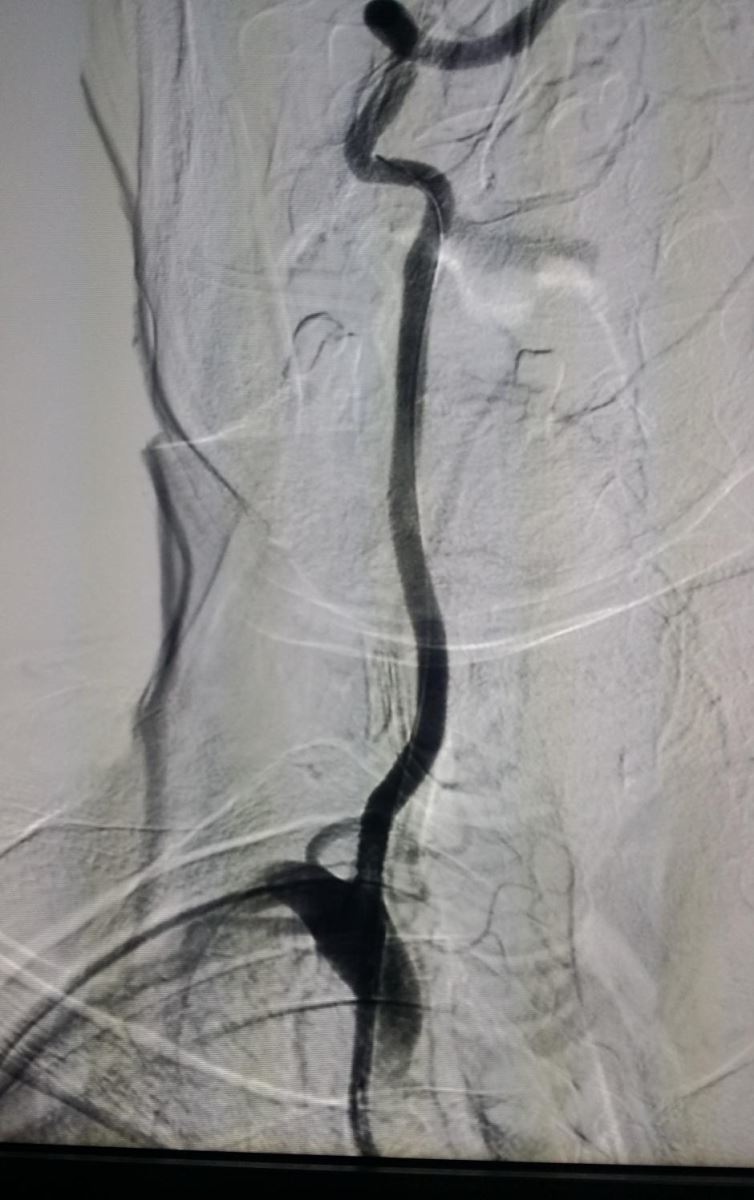

椎动脉支架手术示例(右侧椎动脉起始部):

.jpg)

术前 支架植入后